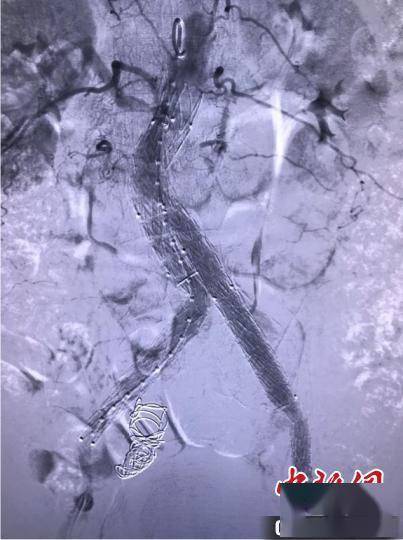

图为手术影像 。西安交大一附院供图

术中 , 杨林副教授团队再次碰到难题 。 患者腹主动脉下段及双髂动脉瘤样扩张明显 , 且双髂外动脉明显迂曲 。 手术团队决定采用双通路、双导丝牵张技术完成覆膜支架系统的输送 。 经过近2小时的不懈努力 , 最终成功为该患者实施了介入微创腔内支架手术 , 造影见腹主动脉并双髂动脉瘤隔绝良好 , 右髂内动脉栓塞良好 , 未见明显造影剂外溢影 。 患者术后症状明显好转 , 已于近日出院 。